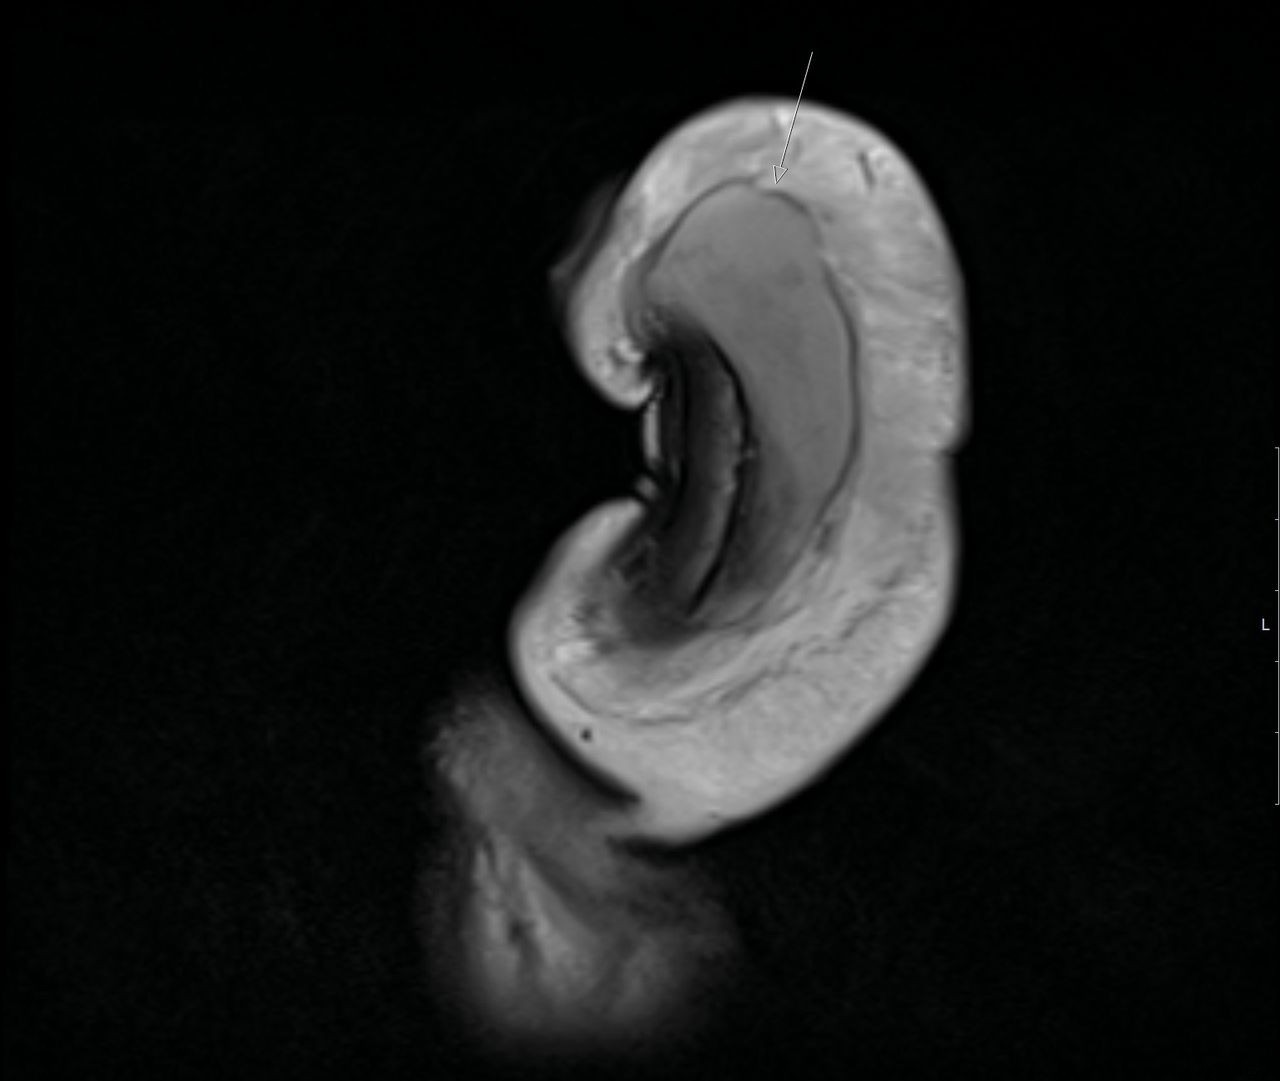

Previously documented fractures featured transverse tears in the tunica albuginea. Now, in a British Medical Journal Case Reports publication, UK urologists describe the first MRI-confirmed vertical penile fracture.

The 40-year-old man sought care after his erect penis bent awkwardly against his partner's perineum during sex. He reported progressive swelling without the typical “pop,” and MRI revealed a vertical tear (top-to-bottom) on the ventral surface of the right corpus cavernosum, spanning about 3 cm (see figures 1 and 2).